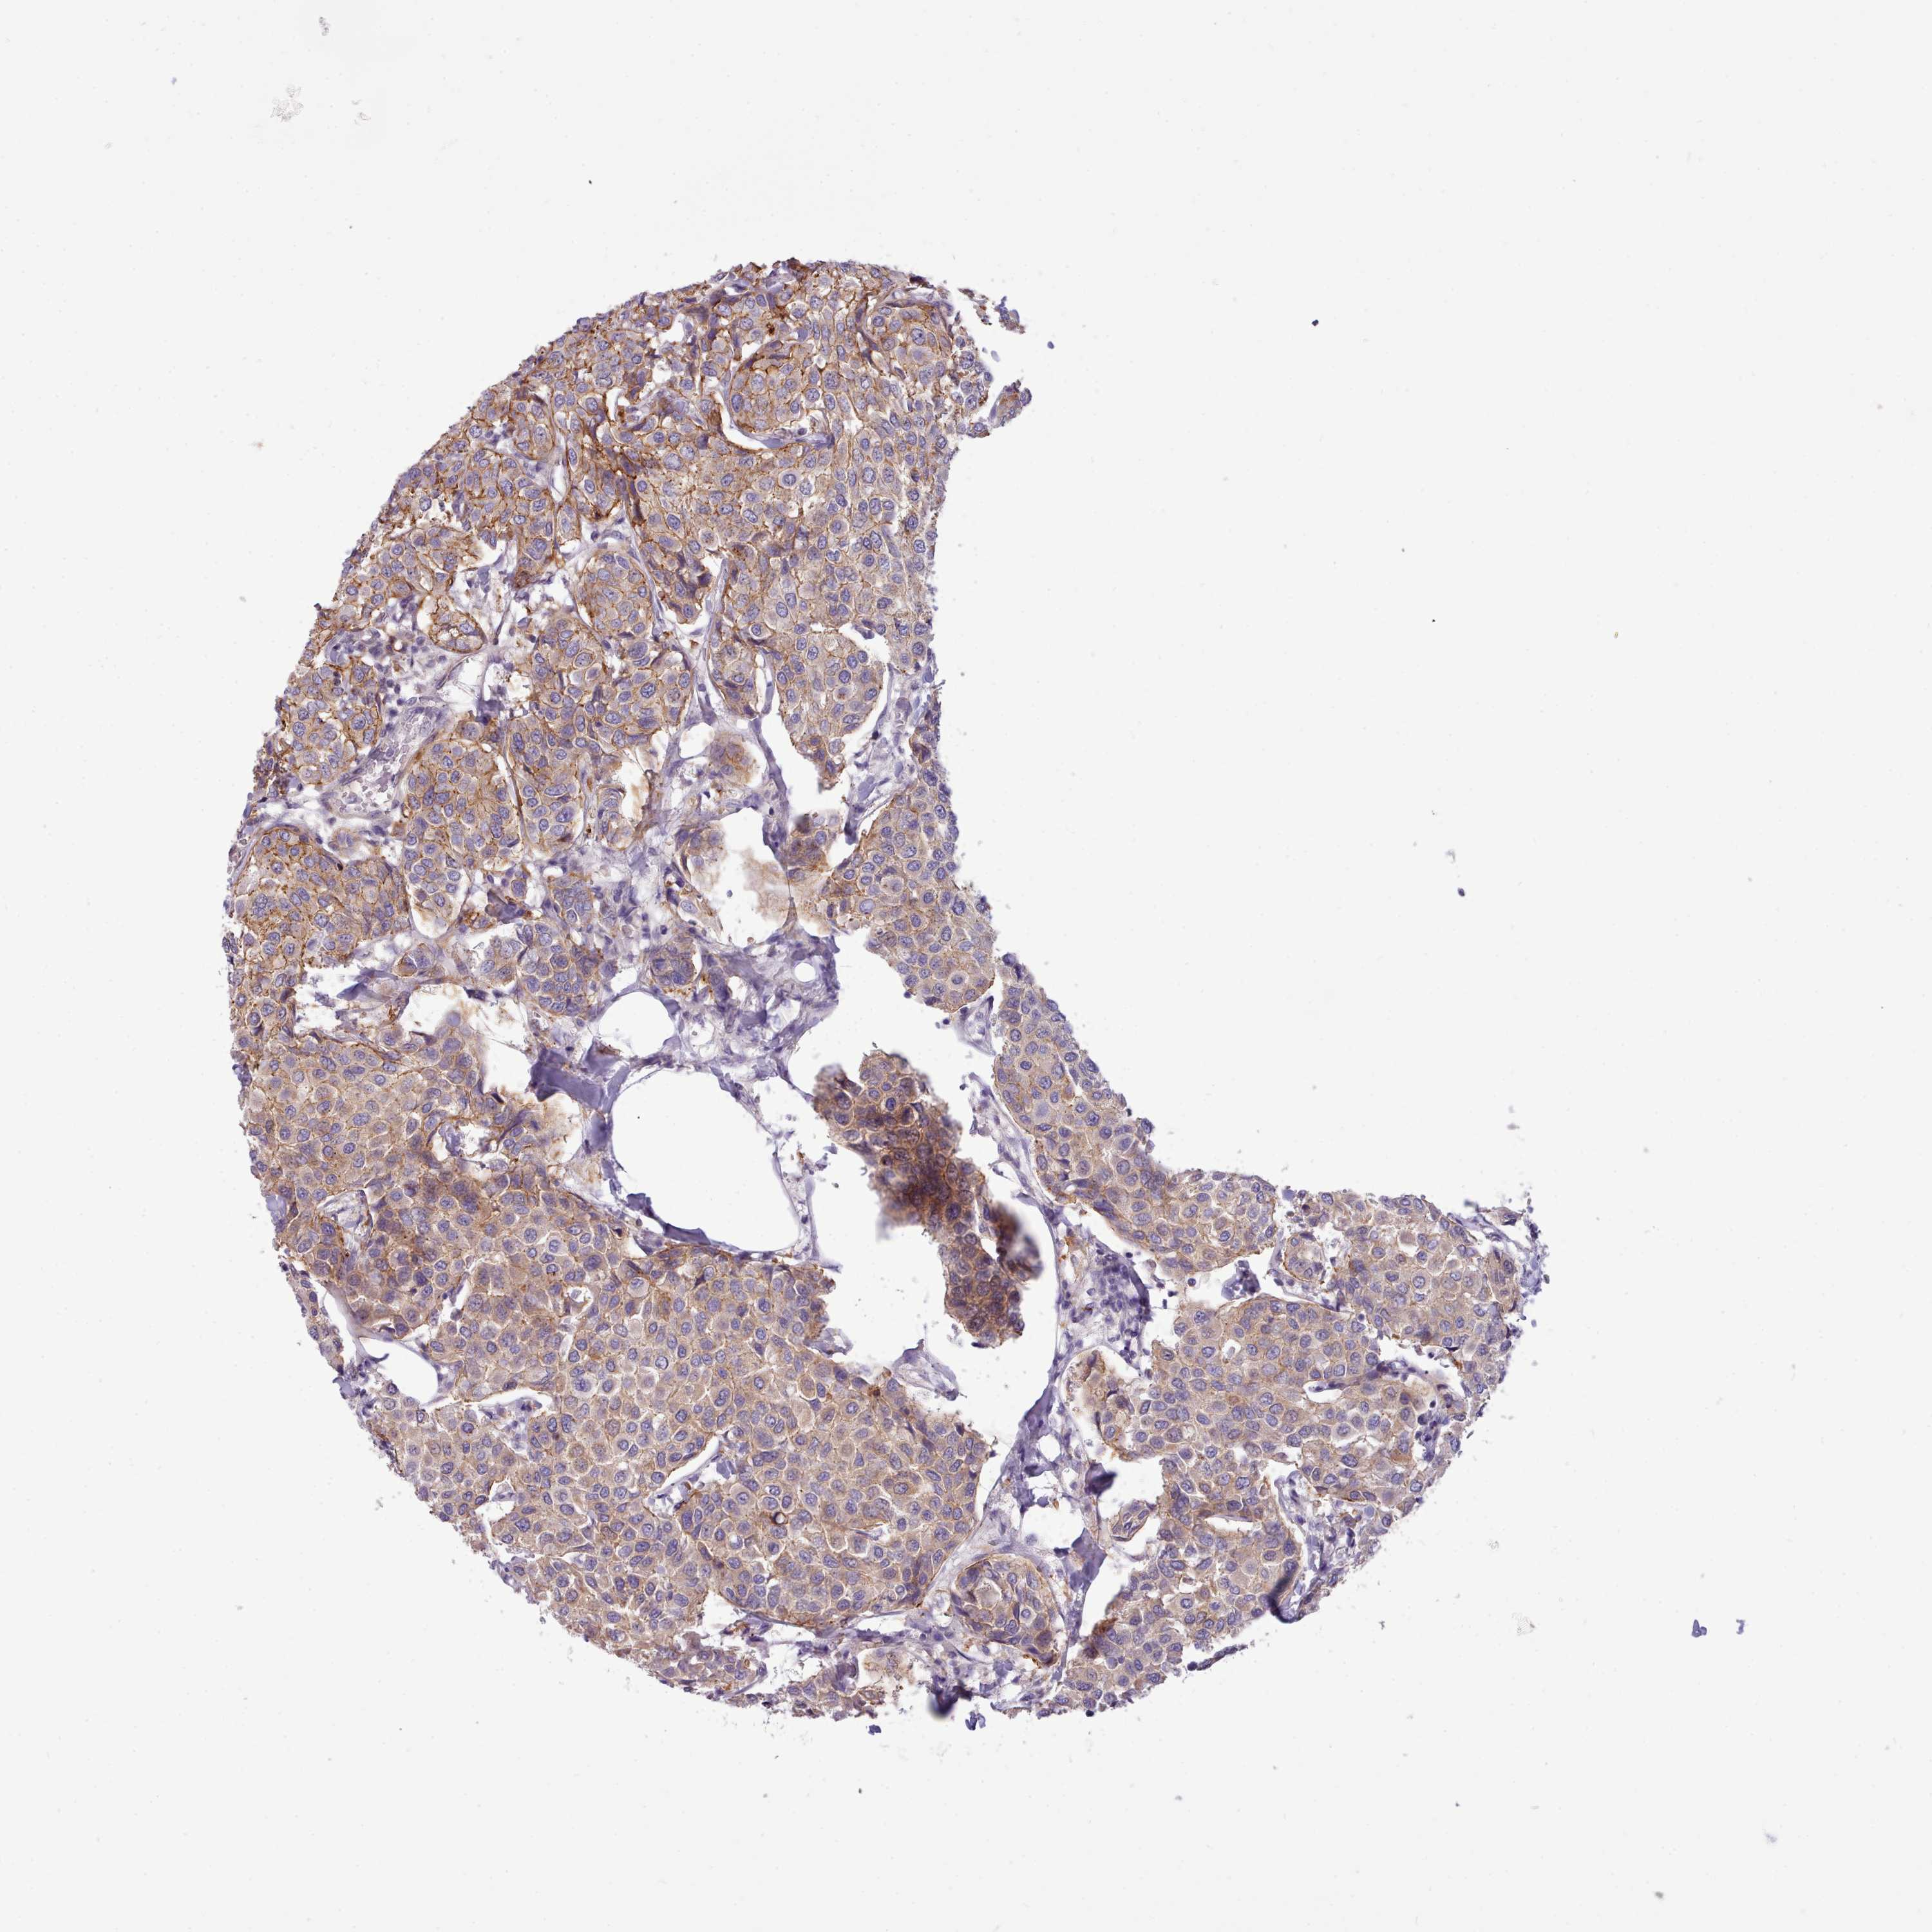

BRCA TCGA BRCA VALIDATION PROTEIN EXPRESSION

ANTIBODIES

AND

VALIDATION